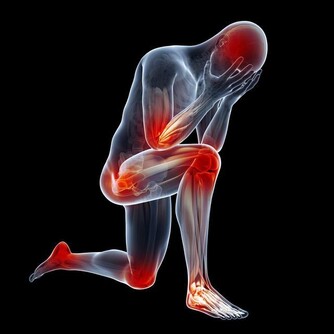

5、頭暈、乏力、嗜睡: 甲醛可影響人的造血系統,輕則引發貧血,嚴重的甚至可能導致白血病。有調查指出,醫院血液科病房中三成以上白血病患者的家庭在兩年內進行過裝修。而兒童因裝修患病的機率更高,佔患病兒童的半數以上。當人體血液供應不足時,就會經常感到疲憊,走路都沒有力氣。因此,入住新居後有頭暈、乏力、嗜睡的症狀,應及時去醫院檢查血常規。